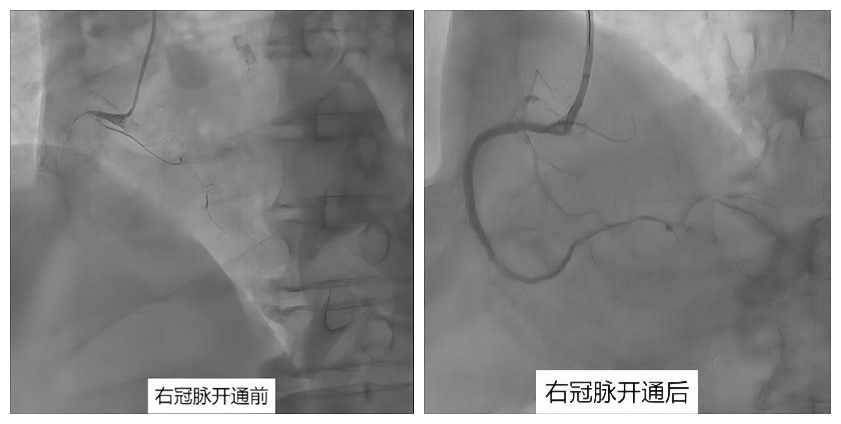

王先生右冠脉血管支架内慢性完全闭塞且严重钙化,左冠脉两根主支血管均重度狭窄,为冠状动脉介入治疗中最为复杂的类型,漯河市中心医院副院长、心内科学科带头人刘东亮教授率介入团队讨论后建议首选外科冠脉搭桥术,但王先生和家属都拒绝做外科冠脉搭桥手术,要求进行微创的冠脉介入手术;在对王先生的冠脉病变进行分析后,最终决定先开通慢性闭塞的右冠状动脉。

经过约半个小时的尝试,导丝成功通过闭塞段到达了右冠脉远端,球囊扩张后做了比冠脉造影更加清晰准确的血管内超声(IVUS)检查,结果显示:右冠脉全程弥漫性病变,多处钙化混合斑块,支架内再狭窄严重,球囊扩张效果不佳;为了获得更加理想的血管管腔,我们使用准分子激光对闭塞的右冠脉施行了经皮冠状动脉腔内激光成形术,做了4次激光斑块消蚀后,再次做IVUS检查发现右冠脉血管病变处管腔明显增大。

因为右冠脉闭塞时间太长,血管已经萎缩变细,且病变非常弥漫,再次植入支架发生再狭窄及闭塞的可能很高,所以激光消蚀后又使用切割球囊对病变进行扩张,最后植入了药物球囊,最终的造影结果非常理想。